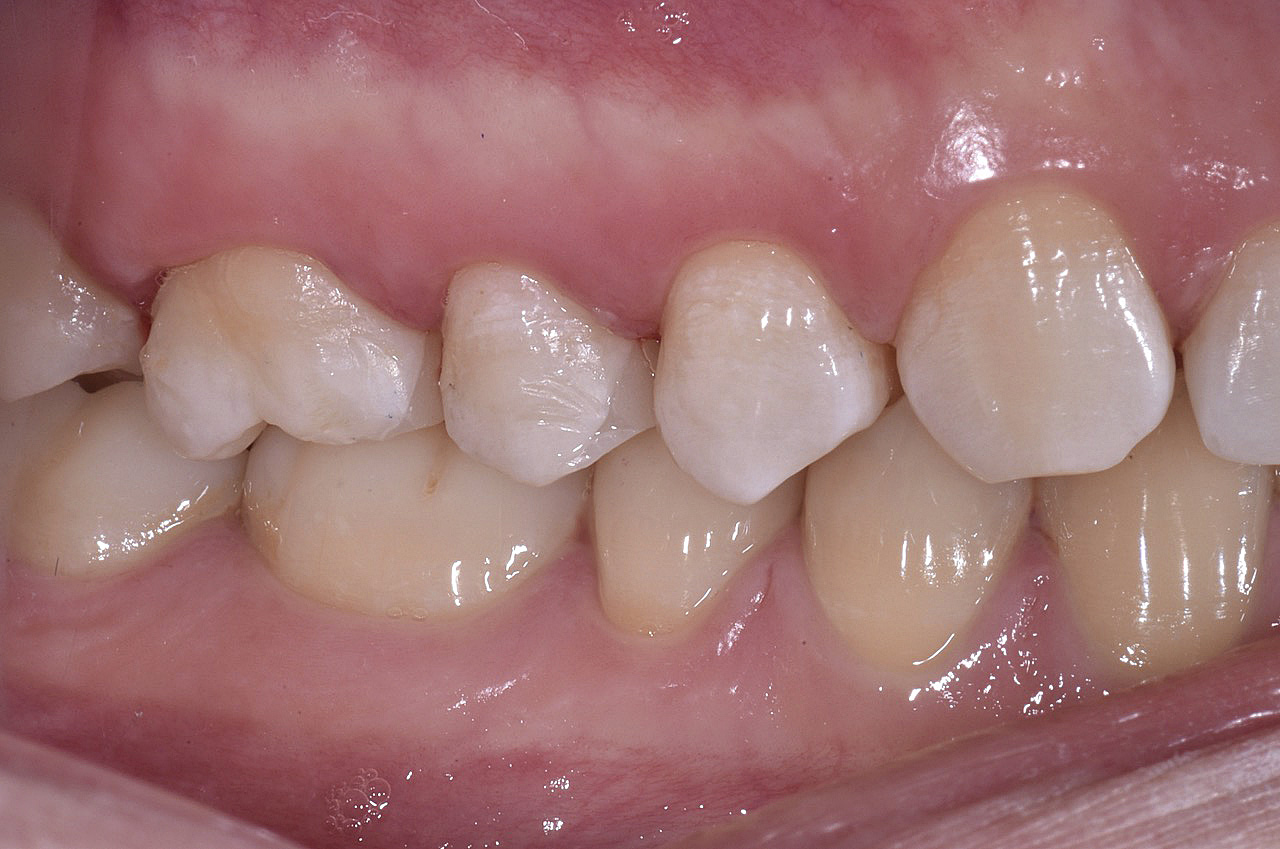

PREMESSA: in seguito all’estrazione dell’incisivo laterale superiore di destra, resasi necessaria per cause batteriche, si decide di affrontare il caso con il posizionamento di un impianto in sostituzione dell’elemento mancante dopo guarigione del sito infetto. Con tecniche rigenerative sia dei tessuti ossei mancanti a causa dell’infezione pregressa, sia dei tessuti gengivali che appaiono inizialmente troppo spostati in alto, si ripristina una corretta morfologia delle parabole (contorni) gengivali e delle papille interdentali (triangoli di gengiva tra due denti vicini).

Vengono utilizzati 2 tipi di provvisori: il primo, cementato ai denti vicini, viene utilizzato dal momento dell’estrazione del dente fino ad impianto osteointegrato (circa 6 mesi); il secondo, avvitato direttamente all’impianto, ha una funzione di prova estetica ma soprattutto di guida per la maturazione dei tessuti gengivali peri-implantari portandoli verso la maturazione completa prima di posizionare la corona finale in disilicato di litio.